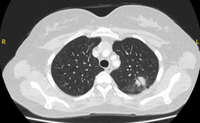

Computed tomography (CT) showing two left lower lobe peripheral nodules (one slightly spiculated and the other with smoother margins) in a patient presenting with fever, high inflammatory serum markers, and blood cultures confirming Streptococcus intermedius. Both nodules completely resolved following a course of linezolid, consistent with septic emboli

From the collection of Dr George Tsaknis, MD, PhD, FRCP(London), MRQA, MAcadMEd, PGCert; used with permission